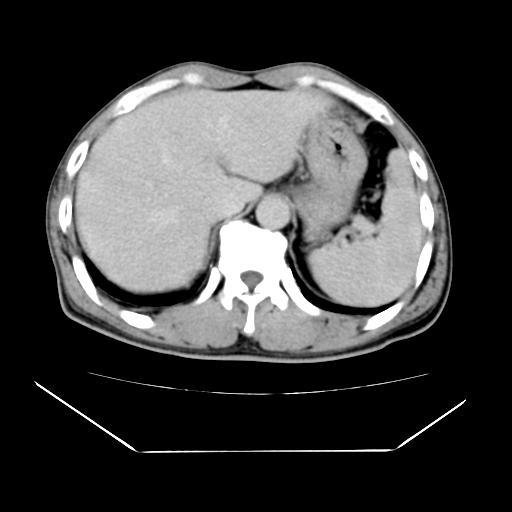

男性,55岁,外院体检afp明显升高,但b超未发现异常,否认乙肝病史。来我院ct增强。有延时扫描。

肝脏右叶动脉期可见低密度影,至延迟期被充填,考虑血管瘤可能性大。

肝右叶病灶

不排除肝右叶肝癌可能。

这个不是肝右静脉吗,这么大的病灶b超不可能发现不了吧

如果这个是癌灶的话则下腔静脉有瘤栓可能

肝6段血管瘤

血管瘤可能性大。

是肝右静脉吧

考虑肝右静脉影。